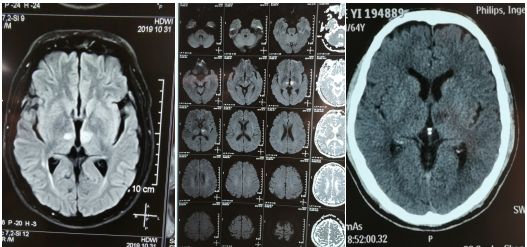

CT和核磁共振证实双侧丘脑梗死

患者恢复意识后,复查脑CT溶栓时没有发生颅内出血并发症,核磁共振提示双侧丘脑梗死,符合入院时医生判断,这是一个极少见的梗死,丘脑梗死极少同时双侧发生梗死。